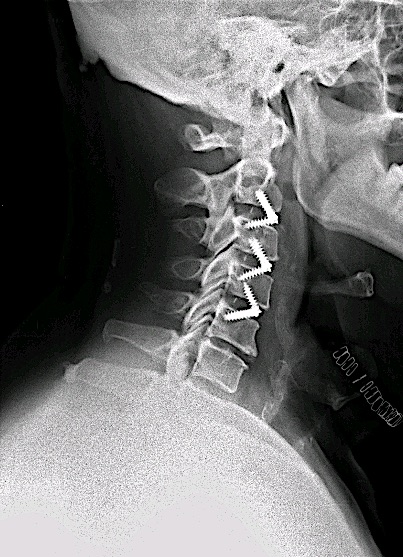

El paciente fue intervenido vía anterior, con monitorización neurofisiológica intraoperatoria, sin incidencias.

El control postoperatorio RM cervical 6 meses demuestra adecuada descompresión de canal y adecuada aceptación de material de osteosíntesis.